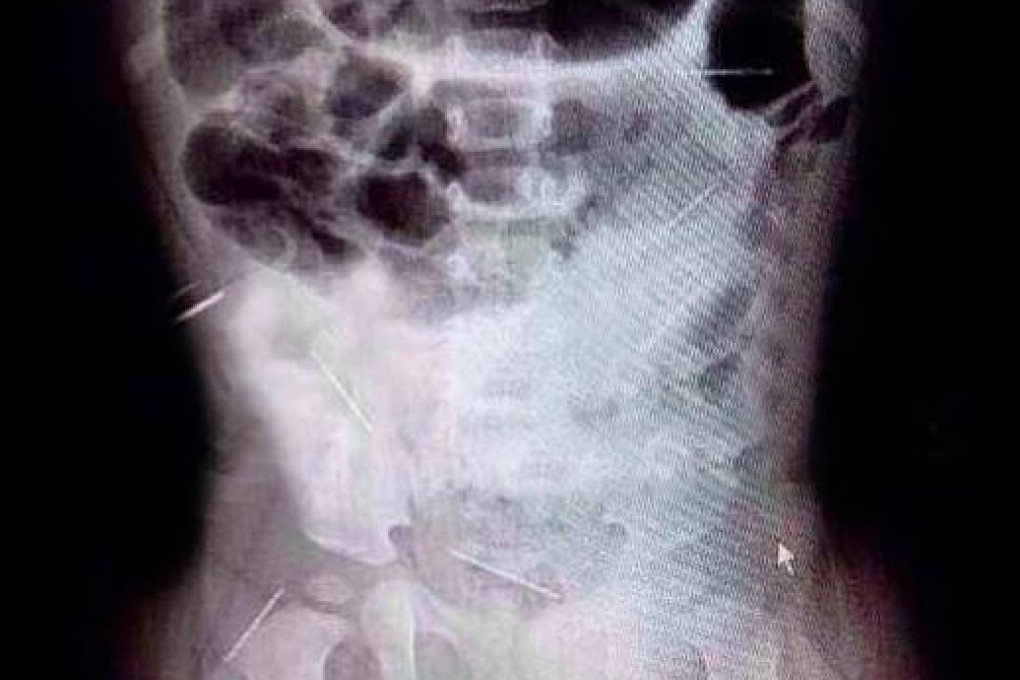

Doctors have decided to surgically remove three life-threatening sewing needles which have pierced dangerously close to the heart of an 11-month-old girl – and leave nine more alone amid fears removal would be too risky.

The girl was taken to the capital via high-speed train after X-rays showed she had 12 sewing needles insider her body – just one month after four needles had been found inside her.